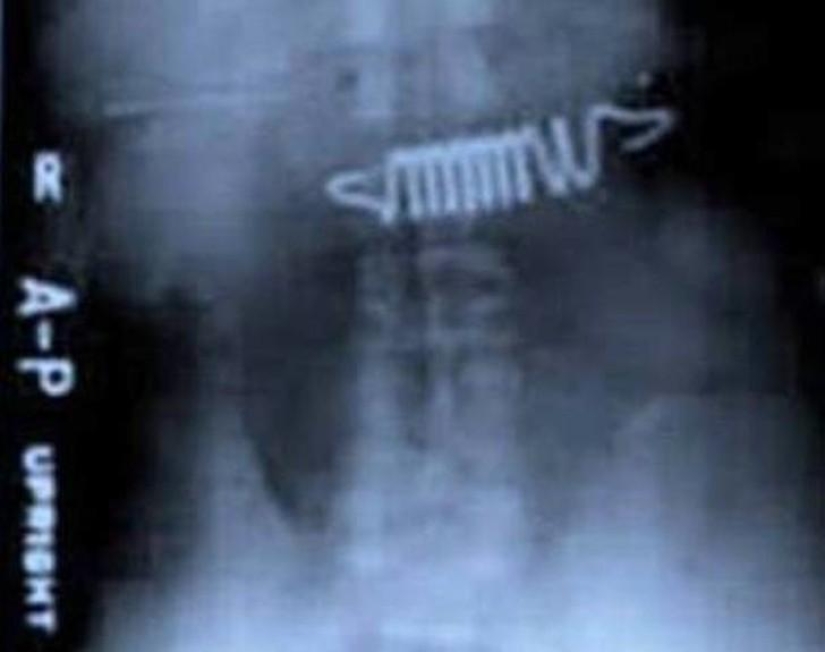

Bed springs.